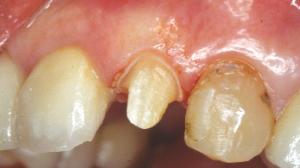

Le but de cet article est de proposer une démarche simple, applicable à la plupart des situations cliniques en dentisterie esthétique. Présentation du cas: Restauration de 22 et 23. Sur la 22, une préparation coronaire périphérique en vue d'une couronne céramo-céramique a été réalisée.

Présentation du cas : Restauration de 22 et 23.

Sur la 22, une préparation coronaire périphérique en vue d'une couronne céramo-céramique a été réalisée.

Sur la 23, la seule correction à apporter étant la dyschromie, nous allons procéder à la préparation d'une facette avec retour palatin.

Une préparation coronaire périphérique a déjà été réalisée sur la 22.